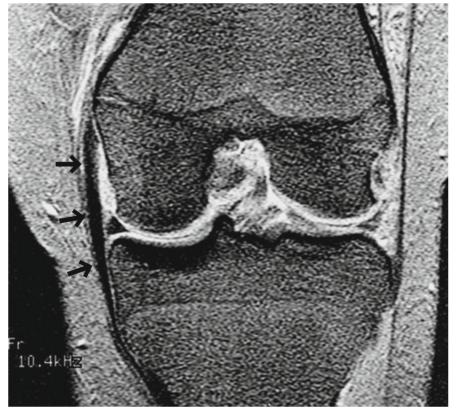

图5.13的慢性撕裂。一个30多岁的女性。冠状T2*WI显示撕裂的MCL被纤维疤痕组织取代并增厚(箭头)。看起来好像是一个正常的MCL。解释这类案例时需要谨慎